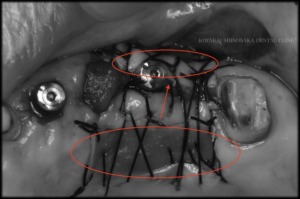

治療前

まず義歯を支えるために、左上3と5の位置にインプラントを埋入する予定で治療を進めていくことになりました。

埋入した後は結合するまでに約3〜4ヶ月の期間を有するのですが、期間中に既存の義歯を使用してしまうと、義歯の構造上、インプラント治療中の部位に影響を与えてしまうため、代わりとして左上1から7まで連結した仮歯を作製しました。

しかし、問題のある歯は仮歯の真ん中に位置しており、この歯を無くしてしまうと連結した仮歯を支える歯が左上1と7だけとなり、間に歯がひとつも無い状態となるため、維持していくのが難しくなることが懸念点でした。

患者さまとご相談の結果、仮歯の維持を優先し、抜歯の前にインプラント2本の埋入から進めることにいたしました。治療箇所の治癒を待った後、インプラントの頭出しの手術を行う際に、主訴である歯(左上4)の抜歯を行いました。

また、左上5ー7上部の角下歯肉が減っていたため、インプラントの頭出しと同じ日に、歯肉移植【FGG(遊離歯肉移植術)】も行いました。